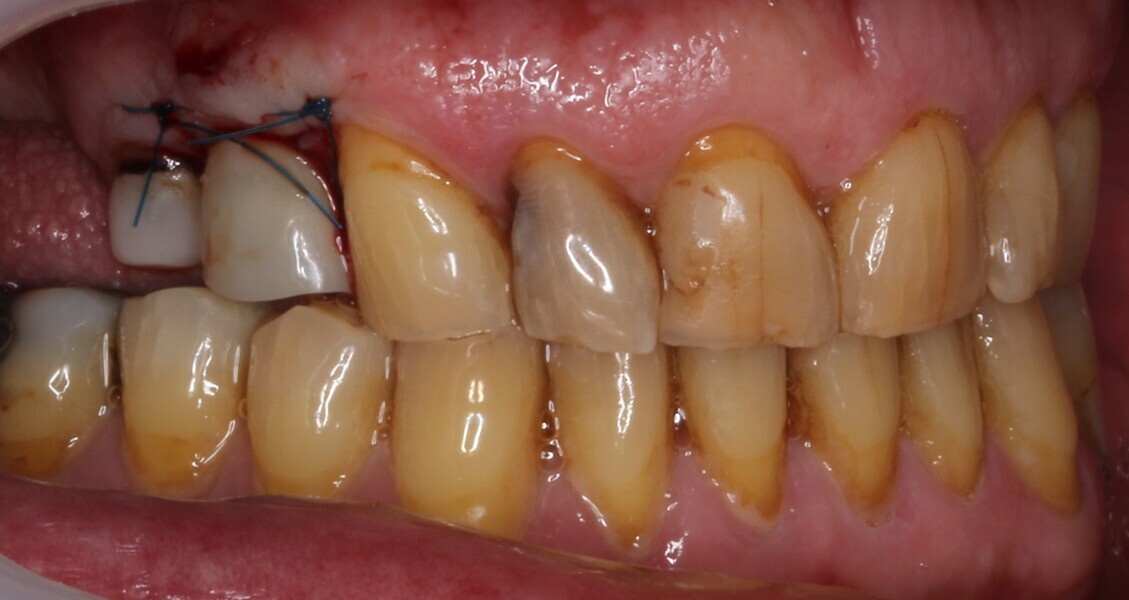

The fit of the surgical guide was confirmed, and the patient was anaesthetised locally (Fig. 15). A small full-thickness flap was raised, and a guided osteotomy was performed. The implant was inserted to a 45 N cm torque. The prefabricated two-piece provisional restoration was torqued in to 15 N cm and was confirmed to be out of occlusion. Two 4-0 PROLENE sutures (Ethicon) were used to close the flap (Figs. 16–19).

Endodontic therapy was commenced on tooth #15 in the meantime. The sutures were removed 14 days later, and the patient reported uneventful postoperative healing at this stage.

Fig. 17: Provisional restoration in place after implant placement.

Fig. 18: Post-op situation.